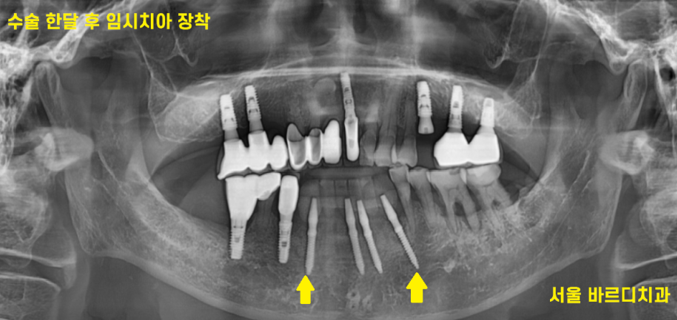

230725

수술 한 달 뒤 사진입니다.

앞니는 무엇보다도 중요한 것이 예.뻐.야 합니다.

남녀노소

연령 상관없이 예뻐야합니다. (몹시 중요)

기능적으로는 면을 자르는 정도이지만

눈으로 잘 보이는 부위이기 때문에

환자분의 사회 생활을 위해

임시치아를 만들어드렸습니다.

앞니 임플란트 후 3-4개월은

치아 없이 쓰셔야 하는데

남들에게 이 없는 모습을 보여주기가 참 어렵죠~

강동구 치과에서는 환자분에 사정에 맞춰

임플란트 치료 후 임시치아를 제작해 드립니다!!